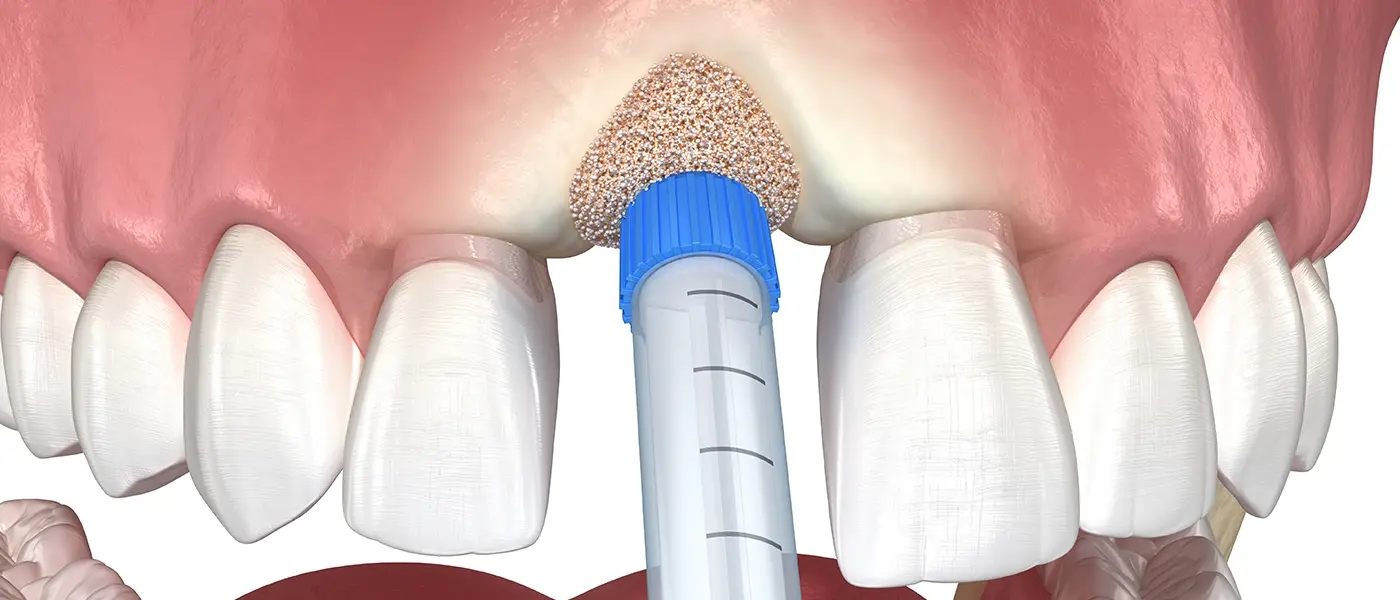

Early-stage gum disease (gingivitis) can often be managed with a professional cleaning and improved home care. More advanced disease may require scaling and root planing, surgical pocket reduction, or regenerative procedures. The sooner you come in, the more options are available — and the more of your natural teeth we can preserve.